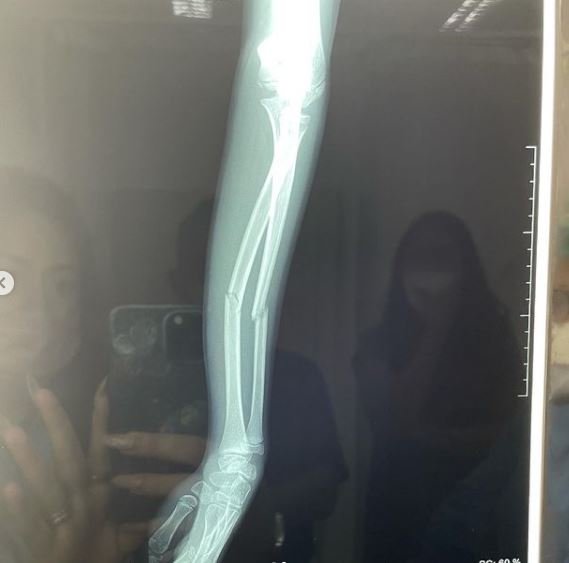

Merdeka.com - Aktris cantik Celine Evangelista kini tengah bersedih usai putri sulungnya, Jemima Guri Clementine Sompie harus menjalani perawatan di rumah sakit. Diketahui, Jemima mengalami patah tulang pada salah satu lengannya.

Hal ini diketahui melalui unggahan terbaru Celine di Instagram pribadinya pada Jumat (11/6) kemarin. Ia memperlihatkan hasil rontgen tangan Jemima. Menangis kesakitan, membuat dokter langsung mengambil tindakan dengan cepat. Kini Jemima harus menjalankan perawatan di salah satu rumah sakit di Malang. Berikut selengkapnya.

Sampai saat ini, belum diketahui penyebab tangan putri Celine Evengelista patah. Ia mengungkapkan kondisi terkini Jemima yang saat ini sedang dirawat dan diberi obat penghilang rasa sakit. Karena sebelumnya, Jemima sempat menangis kesakitan karena menahan sakit pada lengannya.